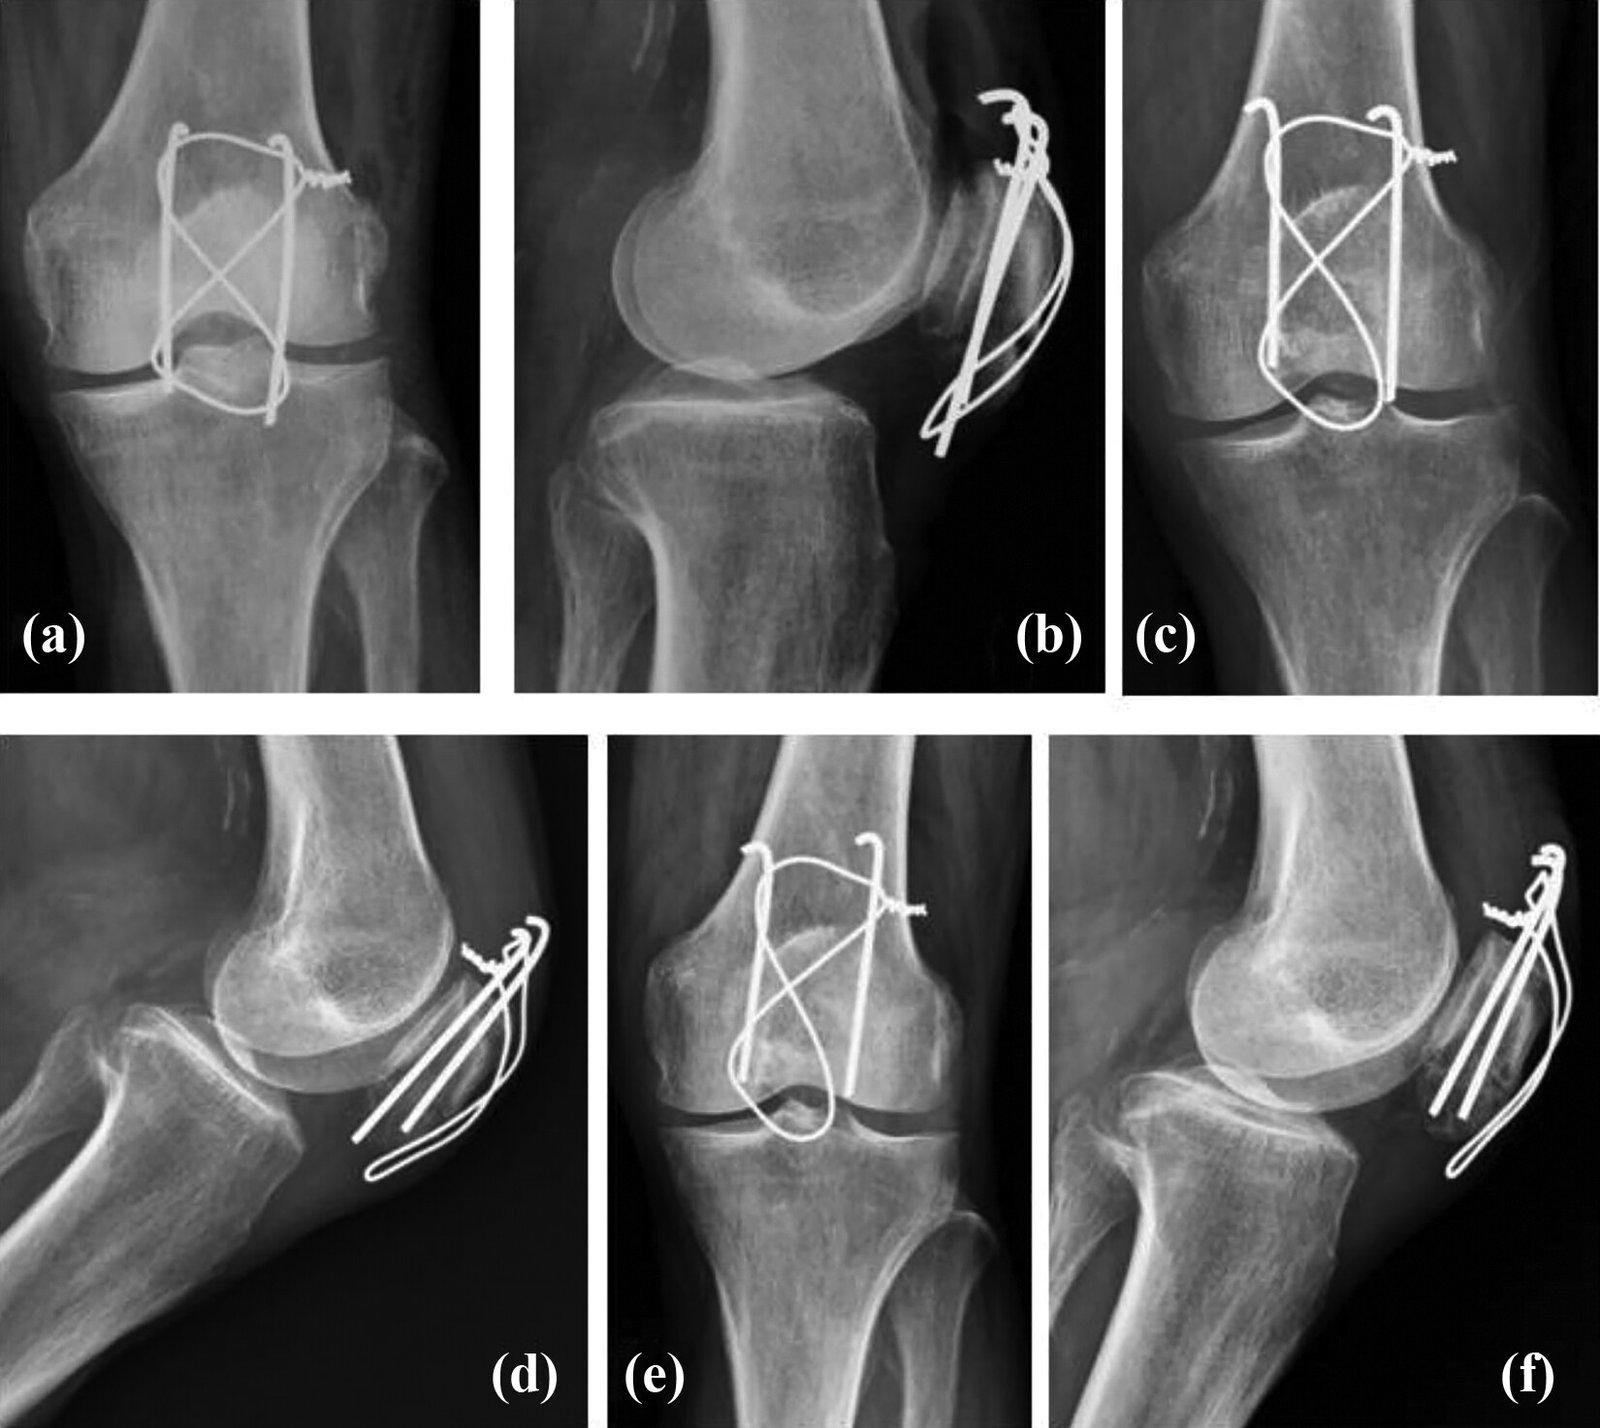

B) Displaced Fracture: In this variety, surgery is the treatment of choice. Surgery is performed as early as possible preferably within 7 days.

1) Open reduction and internal fixation.

2) Patellectomy.

3) Modified tension band wiring (MTBW) (2-K wires with anterior placement).